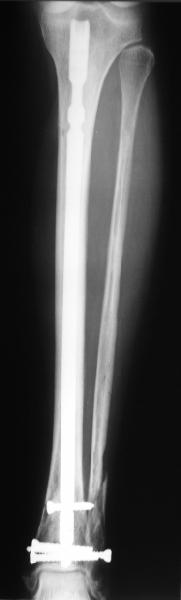

Alexander Chelnokov 22 Май 2006, 00:35

Сделали все-таки стержнем. На всякий случай просверлил дополнительное проксимальное отверстие, так что получилось три 45-градусных винта.

В дистракторе провеи спиц поболше в прокисмальном отделе, чтобы не разобщить фрагменты при сгибании колена. Комментарии и критика приветствуются.

We proceeded with nailing using a small wire distractor, with few wires at the proximal end to prevent displacement with forced knee flexion. Images attached. Comments and critics are welcome.